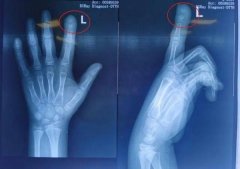

• 神奇!新生儿出生后右手食指现创口,原来竟是自己在妈妈肚子里嘬破的,3天

食指 男宝 水疱 2024/07/23

• 哭笑不得!新生儿在妈妈肚子里将手指嘬破

水泡 食指 子宫 2024/07/26